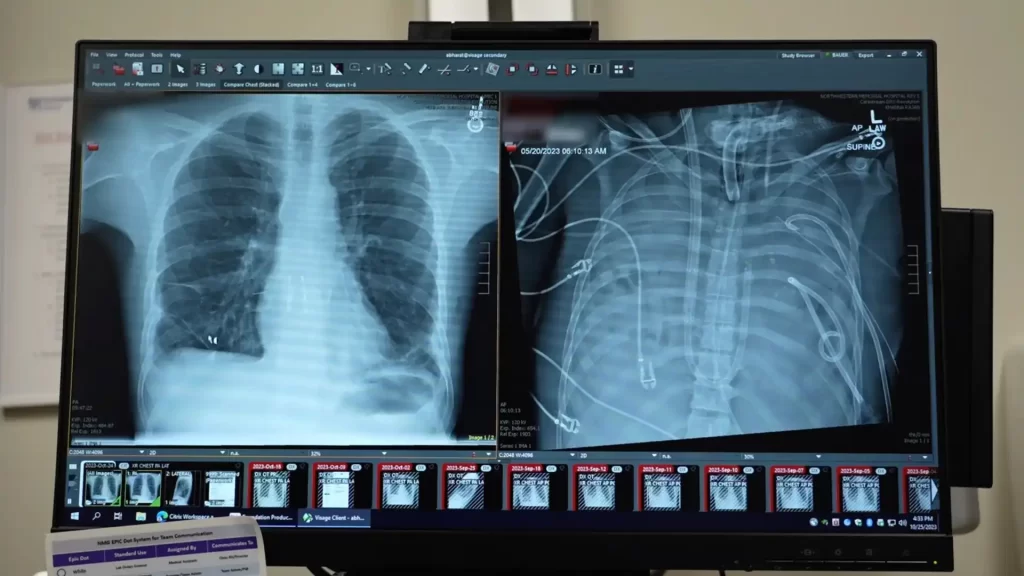

Em um relatório publicado na revista Med, da Cell Press, cirurgiões detalham como removeram os pulmões gravemente infectados de um homem e utilizaram um sistema de “pulmão artificial” para mantê-lo vivo até que um transplante duplo de pulmão pudesse ser realizado. O caso destaca uma nova maneira potencial de manter pacientes em estado crítico vivos enquanto aguardam órgãos de doadores.

O paciente, um homem de 33 anos, desenvolveu síndrome da angústia respiratória aguda (SARA), uma condição perigosa na qual a inflamação e a infecção sobrecarregam os pulmões. Sua doença começou com uma gripe, que rapidamente piorou e foi complicada por uma pneumonia bacteriana. À medida que seu quadro clínico se deteriorava, seus pulmões, coração e rins começaram a falhar. Nesse ponto, um transplante duplo de pulmão tornou-se sua única chance de sobrevivência.

Os pulmões do homem estavam irrecuperáveis e contribuíam ativamente para a disseminação da infecção. No entanto, seu corpo estava instável demais para suportar um transplante imediato, então os médicos precisavam de tempo para estabilizá-lo.

Para solucionar esse problema, a equipe médica desenvolveu um sistema de pulmão artificial projetado para assumir temporariamente a função dos pulmões. Esse sistema oxigenava o sangue, removia o dióxido de carbono e auxiliava a circulação, permitindo que o coração e outros órgãos continuassem funcionando mesmo sem pulmões.

Após a remoção dos pulmões danificados, o estado do paciente começou a melhorar. Sua pressão arterial estabilizou, seus órgãos começaram a se recuperar e a infecção foi controlada. Dois dias depois, pulmões de doadores ficaram disponíveis e os cirurgiões realizaram com sucesso um transplante duplo de pulmão. Mais de dois anos depois, o paciente vive uma vida normal com função pulmonar saudável.